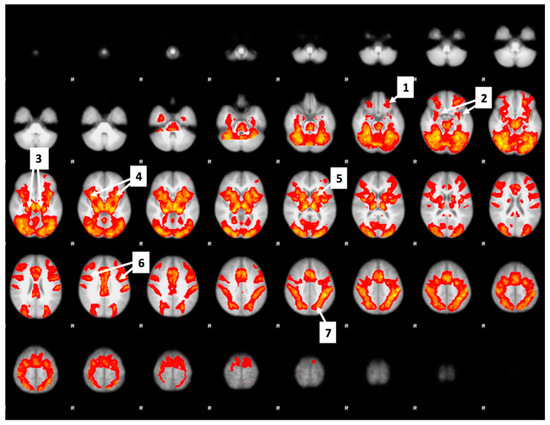

3.8. Bid-Correlated Brain Activity during Food Valuation Period